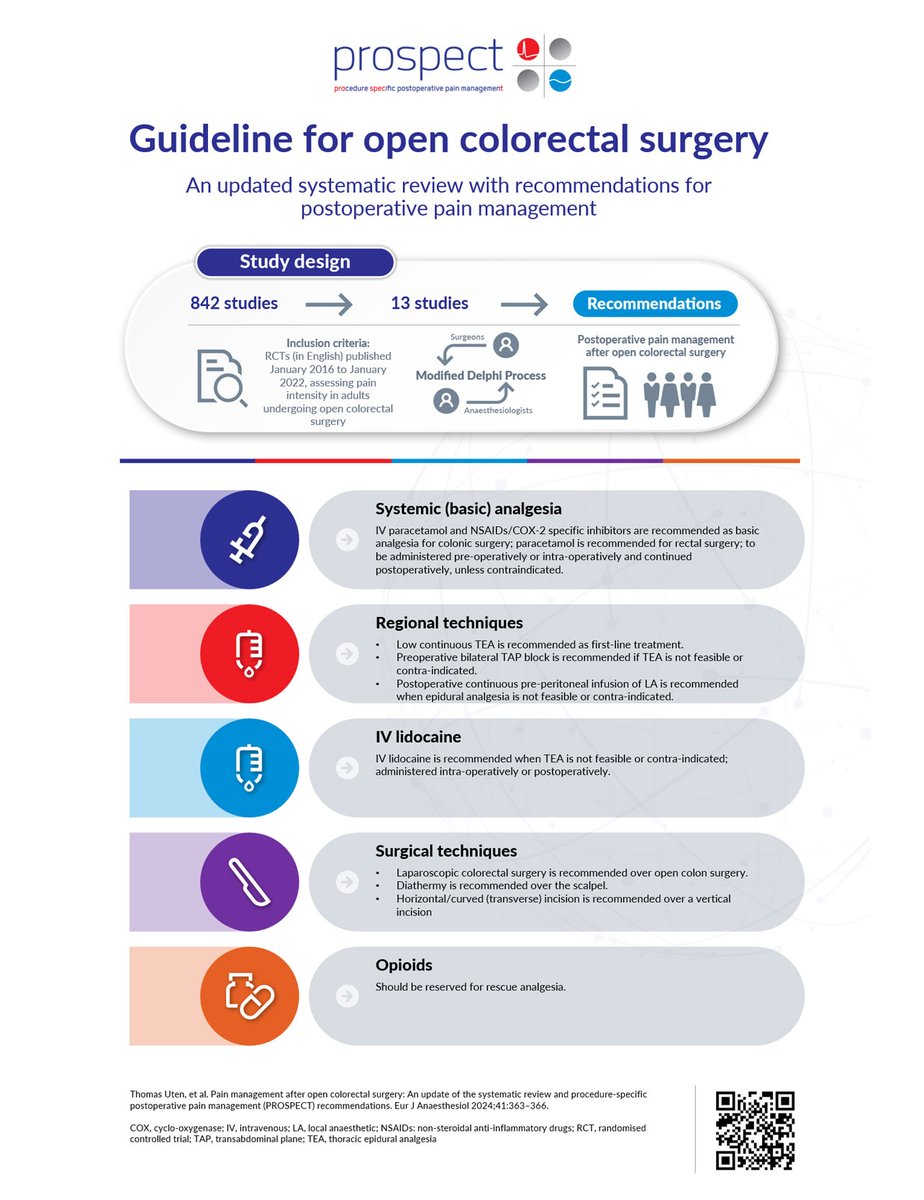

I sent this to my department today as a TL;DR version of the new ASRA Pain Medicine Guidelines on infection control. Feel free to use if it helps! There's a QR code to scan for the full article at the end...